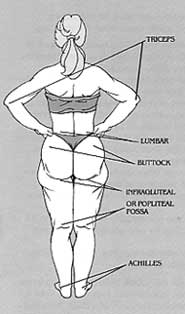

1. Above, the crucial points of fat accumulation on the human body, indicated by the rear.

Diane had swelling and bruises after surgery. This was to be expected, and was a normal result of the trauma of the operation. At slightly over two weeks post-operatively, the swelling was at its greatest. Since I had explained to Diane that this would happen, she was not concerned or worried. I continued to check her at regular intervals, however, and would have removed bandages or tape promptly if there had been any sign they were too tight. By two months after the operation, nearly all swelling had gone down. Diane now had the legs she had been hoping for, ever since she heard about liposuction. Above, the crucial points of fat accumulation on the human body, indicated from the rear.